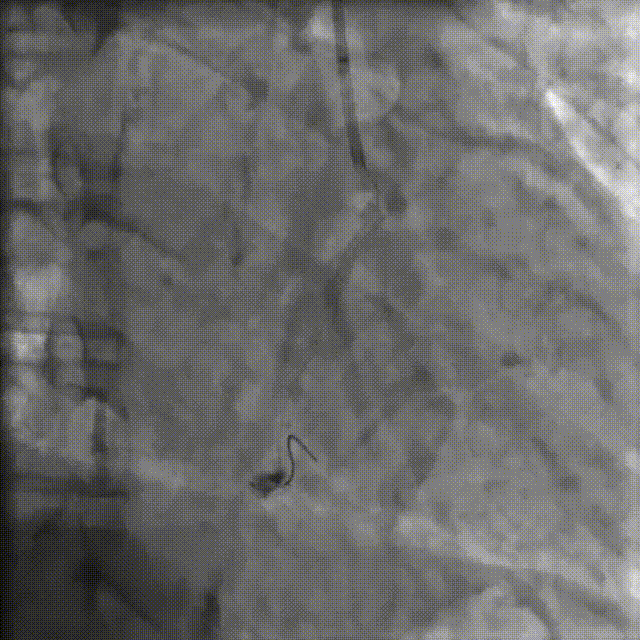

PCI过程-冠状动脉旋切(轨道旋磨)术-1

IVUS导管无法通过,微导管辅助下,将旋磨导丝置于RCA远端,应用1.0mm磨头以13万转反复旋磨钙化病变处(每次15秒,磨头推进速度不超过10 mm/s)

PCI过程-冠状动脉旋切(轨道旋磨)术-2

微导管辅助下,将旋磨导丝置于RCA远端,应用1.0mm磨头以13万转反复旋磨钙化病变处(每次15秒,磨头推进速度不超过10 mm/s)

PCI过程-冠状动脉旋切(轨道旋磨)术-3

共计旋切170秒,术后,狭窄较前减轻